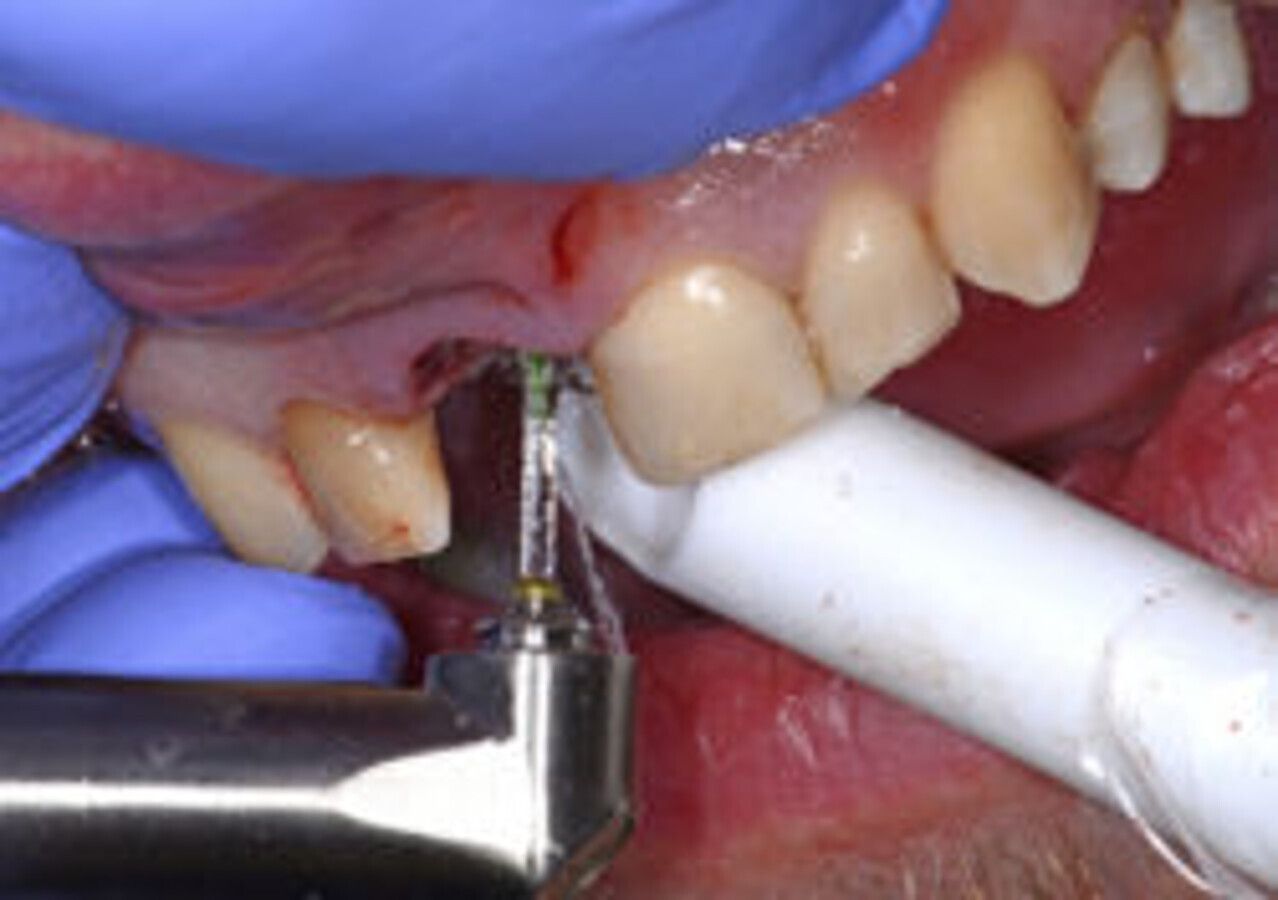

图10. 使用Er:YAG激光治疗仪移除肉芽组织。

前期准备充分后,拔除患牙。患牙骨折吸收区明显可见肉芽组织(图9),使用Er:YAG激光治疗仪将其移除(H14型手持器械,欧洲之星Fotona;图10)。拔牙过程无创伤,创口干洁,可以行种植术(图11)。